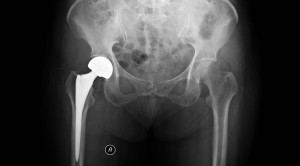

• Efektivitas Hemiarthroplasti dengan vs tanpa Semen dalam Penatalaksanaan Fraktur Intrakapsular Panggul – Telaah Jurnal Alomedika

Efektivitas Hemiarthroplasti dengan vs tanpa Semen dalam Penatalaksanaan Fraktur Intrakapsular Panggul – Telaah Jurnal Alomedika

Cemented or Uncemented Hemiarthroplasty for Intracapsular Hip Fracture Fernandez MA, Achten J, Parsons N, Griffin XL, Png ME, Gould J, McGibbon A,...(Baca Selengkapnya)